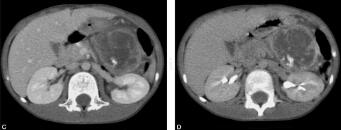

胰腺母细胞瘤(图2)

胰母细胞瘤早期诊断非常困难,影像学检查一经发现肿块往往已经很大。典型的CT表现为胰腺附近实性巨大肿块,最常见的形状为分叶状和球状,分叶状具有特征性但尚不具备特异性,肿块包膜多完整或不完整,边缘多清楚,肿块可强化,常伴有区域性钙化、出血、坏死及囊性变,钙化呈内部束状周边条状,钙化、出血及囊变均没有特征性。MRI表现为不均匀的长T1、长T2信号。由于胰母细胞瘤具有完整或部分包膜,因此肿块在CT、MRI显示的边界往往比较清晰,甚至和邻近正常胰腺组织间界限较清晰,从图像上不能明确判断是胰腺起源,给影像诊断该病带来难度。无论是起源于胰头部还是胰腺尾部,胰母细胞瘤均与胰管没有关系,且常向外生长,不侵袭、压迫胰管,因此胰管在CT、MRI图像上不出现梗阻扩张征象,是为胰母细胞瘤的影像学特点。如果肿块侵袭邻近血管,则可引起癌栓,在增强图像上表现为充盈缺损。